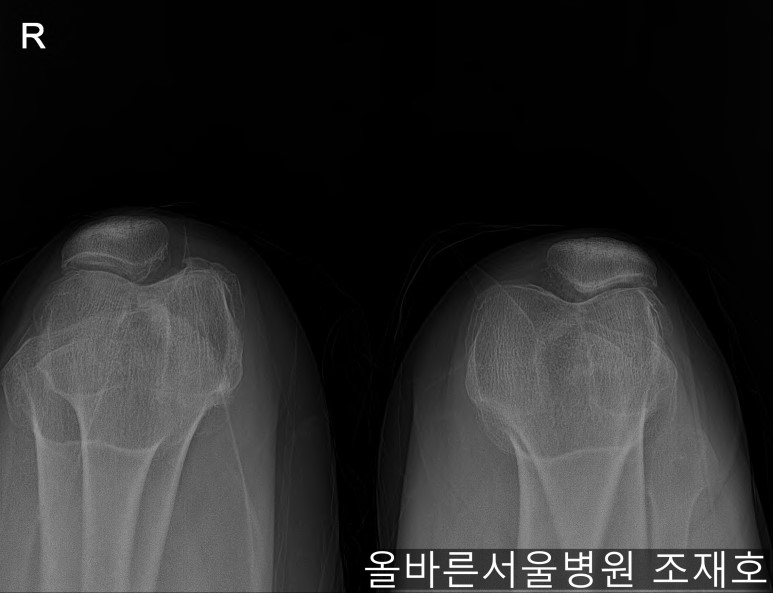

仅通过放射线片子观察到:右膝由于炎症严重,内侧胫骨及股骨已接触在一起,向内测严重变形。

左膝虽然也观察到了炎症,但远不如右膝严重。

如果通过X光片也观察到相同的病症,可以判断内侧关节的软骨大部分都损伤了。

通过观察侧位片子可看到:由于关节炎已经长出骨刺。髌骨关节有炎症。

虽然有髌骨关节炎,但软骨损伤不算严重。